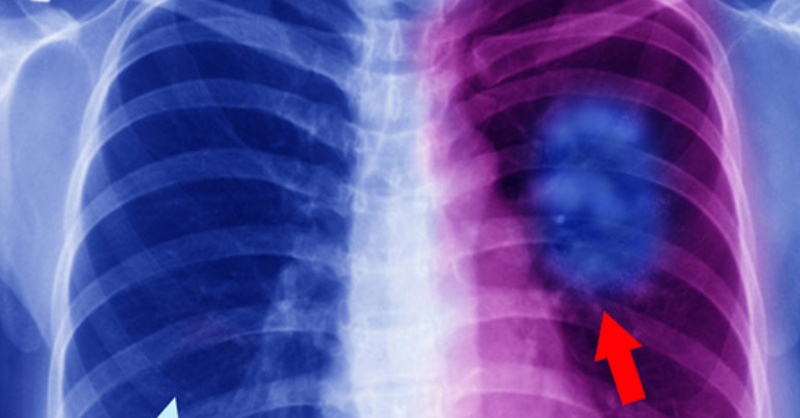

20 Early Warning Signs of Lung Cancer That People Should Never Ignore

Lung cancer is the second most common type of cancer in both men and women. In men, prostate cancer is the most prevalent, while in women, breast cancer...